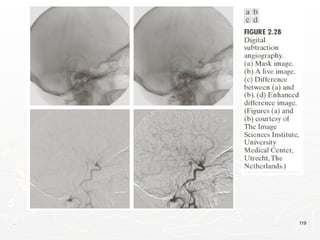

An Example of Image Subtraction: Mask Mode

. 119